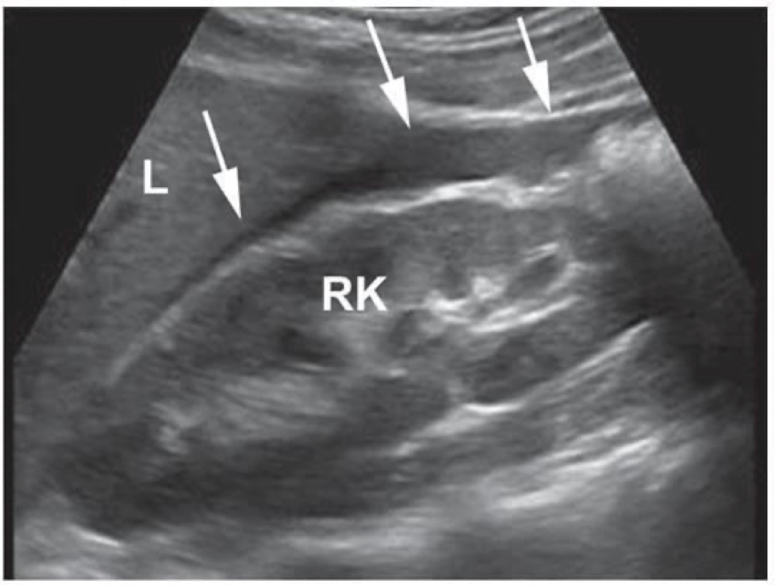

Where is this image showing fluid?

In the hepatorenal space (Morrison’s pouch)